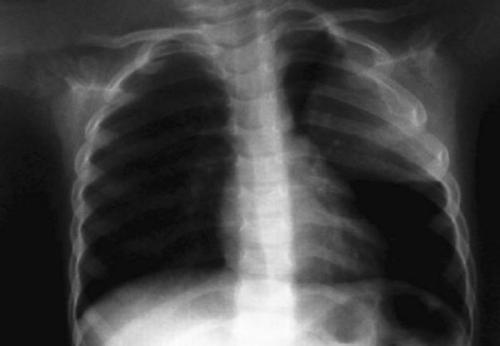

1. RADIOGRAFIA DE TORAX :Es un estudio seguro en el que se utiliza una pequeña cantidad de radiacion para obtener una imagen del torax del paciente. durante el estudio, un equipo d erayos x envia un haz de radiacion a traves del torax y la imagen se registra en una pelicula especial o un computador. esta imagen incluye los organos y las estructuras como el corazon, los pulmones, los grandes vasos sanguineos, el diafragma, parte de las vias respiratorias, los ganglios linfaticos, la parte superior d ela columna vertebral, lasc costillas, la clavicula y el esternon.